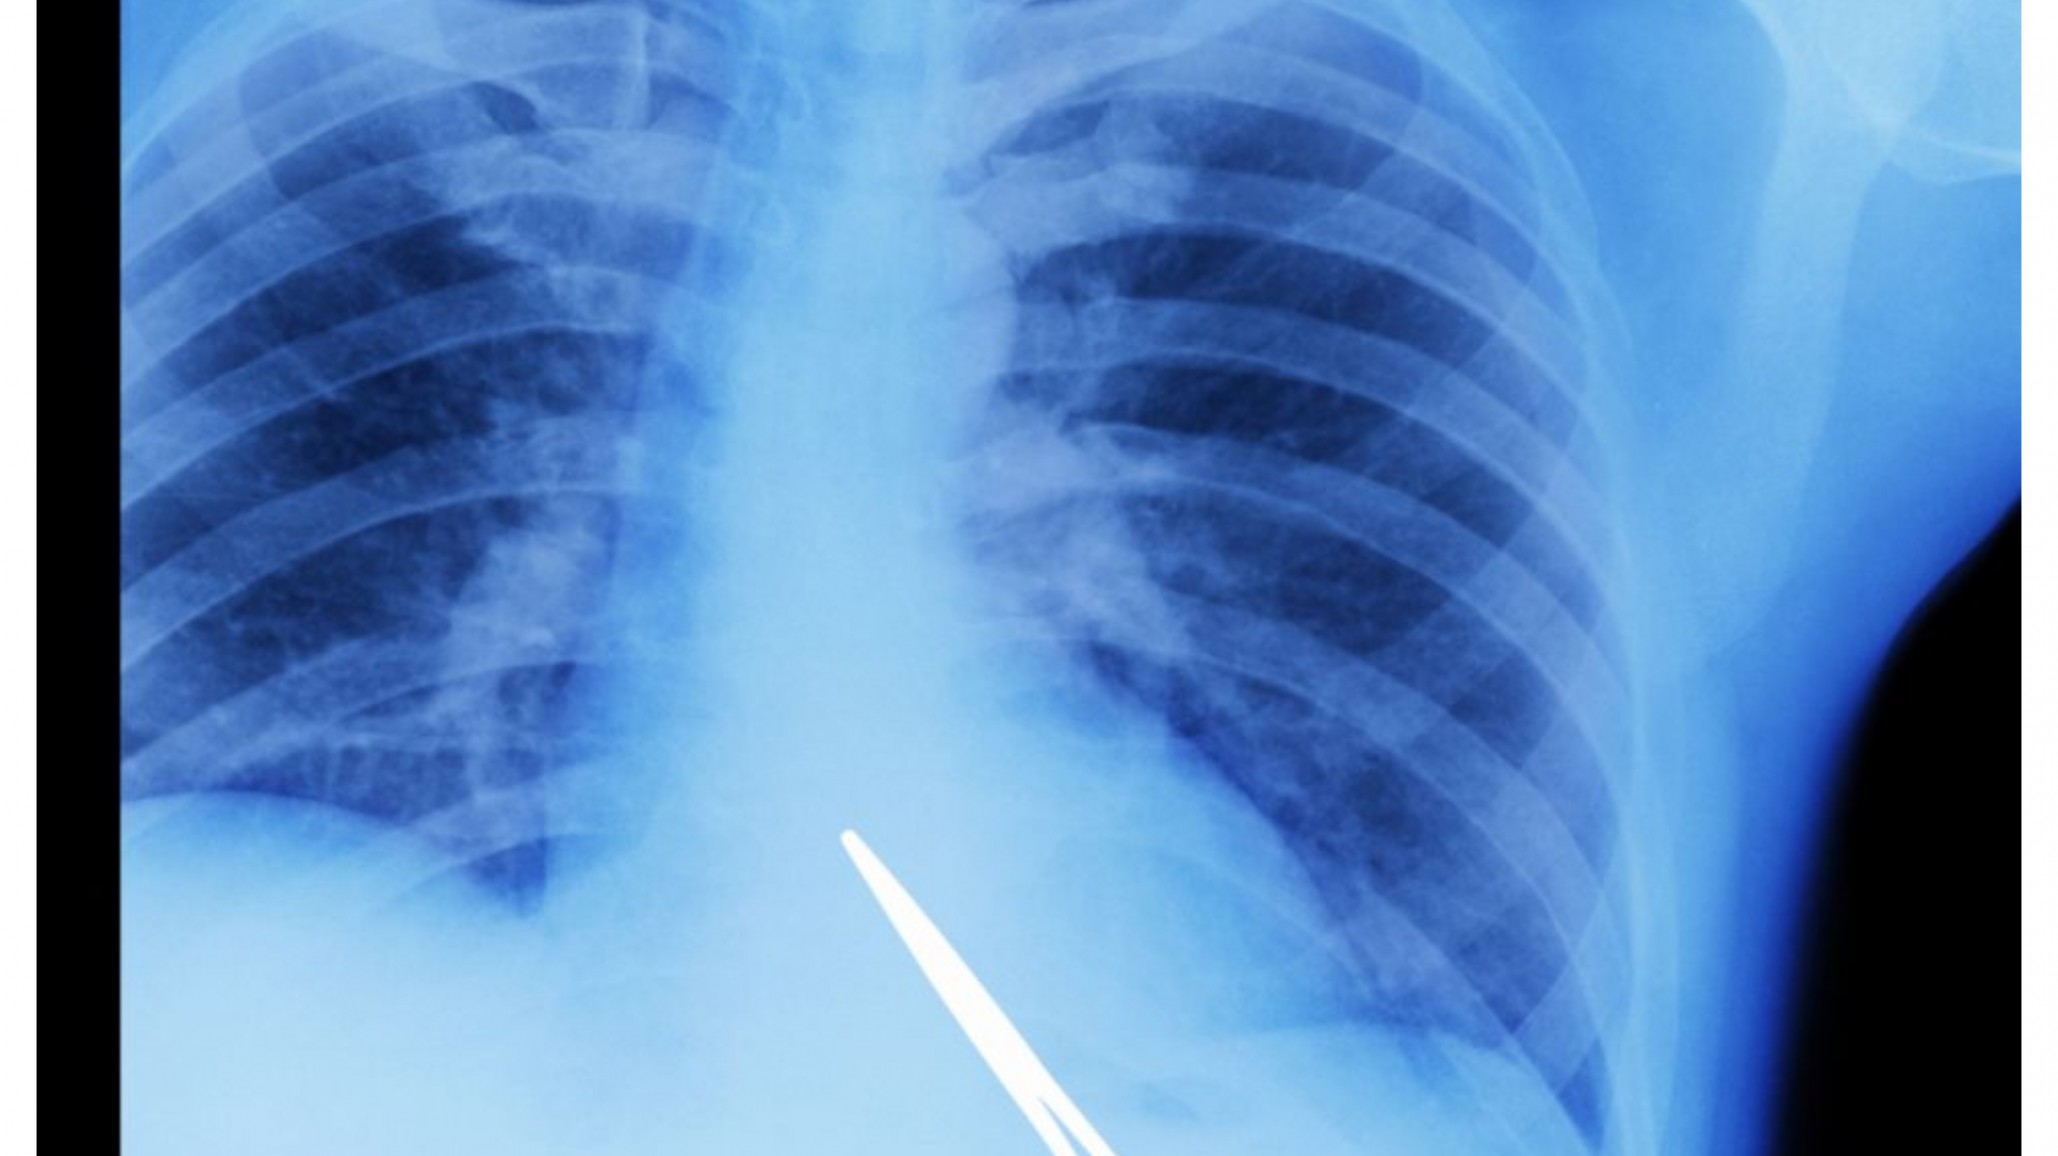

Hasta hace unas semana su vida era normal, hasta que comenzó a sentir molestias y fuertes dolores que le comenzaron a incomodar en la parte donde había sido operado hace ya cinco años. Al realizarse estudios, más precisamente una placa radiográfica, la sorpresa fue grande para quienes hacían los estudios al comprobar que en el interior del hombre había una tijera quirúrgica que habría quedado allí durante su operación.